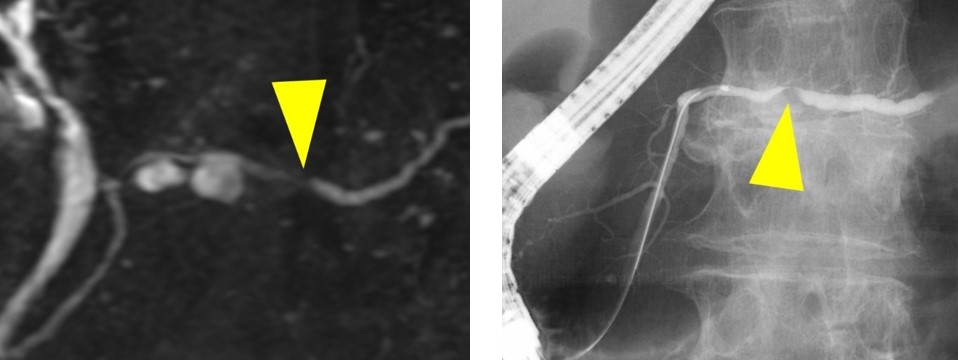

内視鏡的逆行性胆管膵管造影 (ERCP) および磁気共鳴胆管膵管造影 (MRCP) は医療検査です。以下のような胆管や膵管の問題を診断するために使用されます。

MRCP は磁気共鳴画像法 (MRI)技術の一種です。磁石と電波を使用してダクトの画像を生成します。この処置は非侵襲的であり、ERCPとは異なり、放射線を使用しません。

どちらの技術も、膵臓および胆管の問題を検出するために使用されます。診断に使用できる同様の画像が生成されます。

ERCP を取得できない場合は、MRCP を代替として使用できます。 MRCP は、術前処置として ERCP が必要かどうかも判断できます。